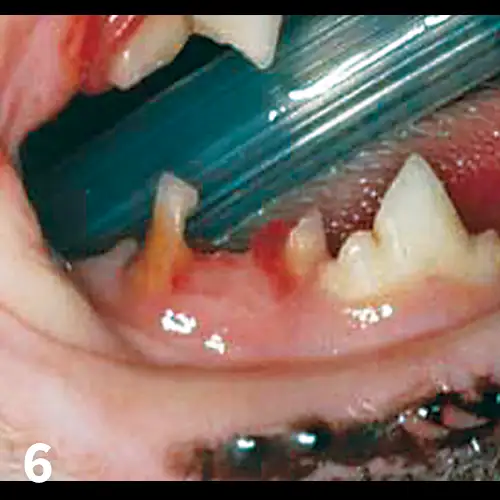

Untreated, the disease may progress to juvenile onset periodontitis, in which plaque and calculus form more rapidly and may result in significant gingival recession, furcation exposure, bone loss, and periodontal pocket formation. (See Figure 2.) Teeth that lose more than 50% support should be extracted.

Feline juvenile periodontitis